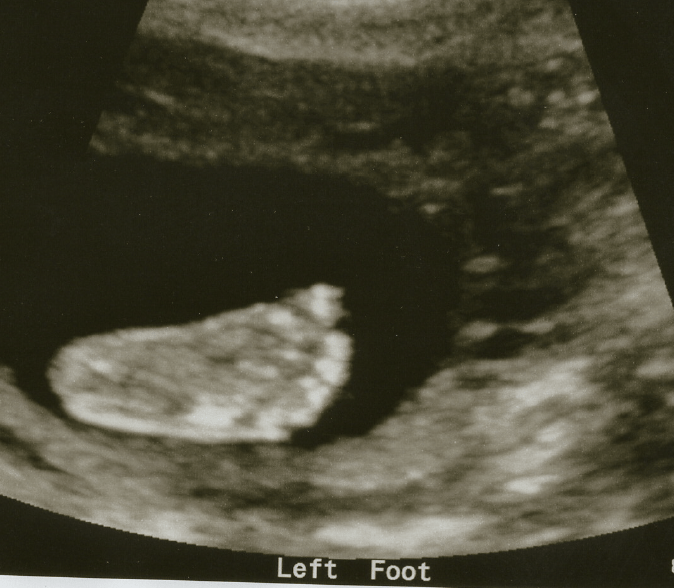

Last Friday, your Dad and I had another routine sonogram. We love going to these doctor’s appointments because we get to see you, or at the very least we get to hear your heartbeat and hiccups and tiny baby noises. This time, we got to see your little tiny features: your eyes, your mouth, your face, your feet and hands. We watched your legs kick, and your arms flail. You made a fist, and spread your fingers wide, too. At the beginning, your feet were almost above my right hip, and your head was on my left. Towards the end, you’d practiced some of your already sweet dance moves and gone almost vertical, with your feet downwards and head upwards.

We watched in awe as the technician maneuvered her apparatus to pull your organs and heart into focus to take images and measurements. She sent us home with your second set of pictures, and MY how much you’ve grown!!